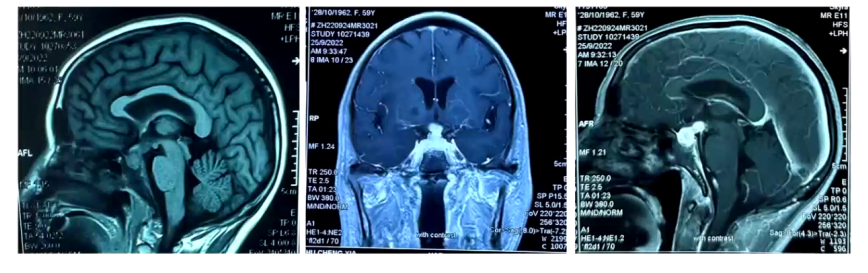

外院头颅MRI:检查显示,9月23日平扫见鞍区及鞍上占位性病变;9月25日增强扫描见垂体区葫芦样异常信号,强化明显,大小约1.9cm×1cm,视交叉略增粗,垂体柄居中,考虑鞍区占位,初步考虑垂体瘤。

治疗第4天,患者入量2850ml,出量1850ml,血钠126.7mmol/L,血钾4.01mmol/L,BNP降低。考虑到患者在糖皮质激素治疗后出现中枢性尿崩症,进一步进行垂体影像学检查,结果显示垂体窝巨大占位较前显著缩小,垂体右缘考虑垂体微腺瘤,神经垂体未见异常,垂体柄增粗并强化,组织细胞增生症待排。